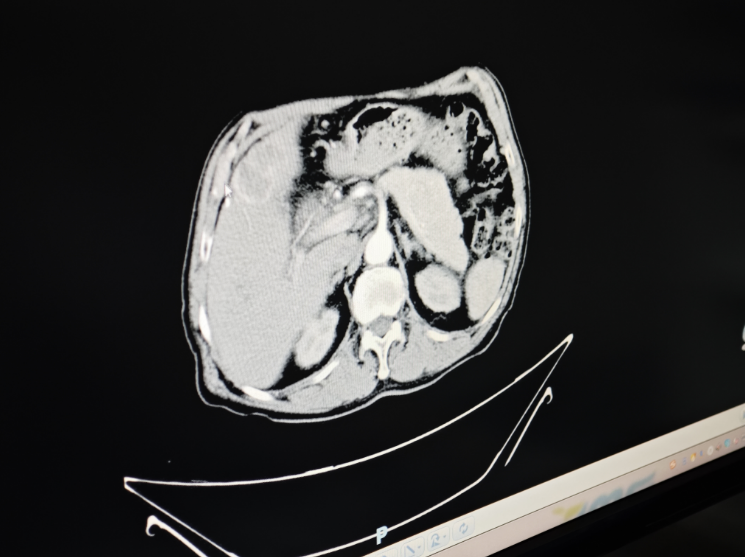

肝脏是人体重要的代谢器官,肝癌是指发生于肝脏的恶性肿瘤,包括原发性肝癌和转移性肝癌两种,人们日常说的肝癌多指原发性肝癌。肝癌是我国死亡人数第二高的癌症,严重威胁着人们的生命和健康。

荆州一医肿瘤三区负责人 副主任医师 杨永华:肝癌跟一些因素有关,首先是乙肝丙肝和肝硬化,还有酒精、糖尿病、黄曲霉菌的感染以及其他疾病导致的肝硬化,包括短期的疾病等等,肝癌在早期是没有明显症状的。

原发性肝癌具有发病年龄轻、恶性程度高、起病隐匿、进展快等特点,其发病早期无特殊症状或痛感。随着疾病进展,患者会表现出肝痛、乏力、消瘦、黄疸、腹水等。

荆州一医肿瘤三区负责人 副主任医师 杨永华:肝癌是可以通过一些手段来预防的,首先接种乙肝疫苗来降低患乙肝的风险,避免肝硬化的出现是可以明显降低肝癌的患病率的,平常也要做体检查彩超,发现早期的病变,我们也可以通过甲胎蛋白筛查来提示。